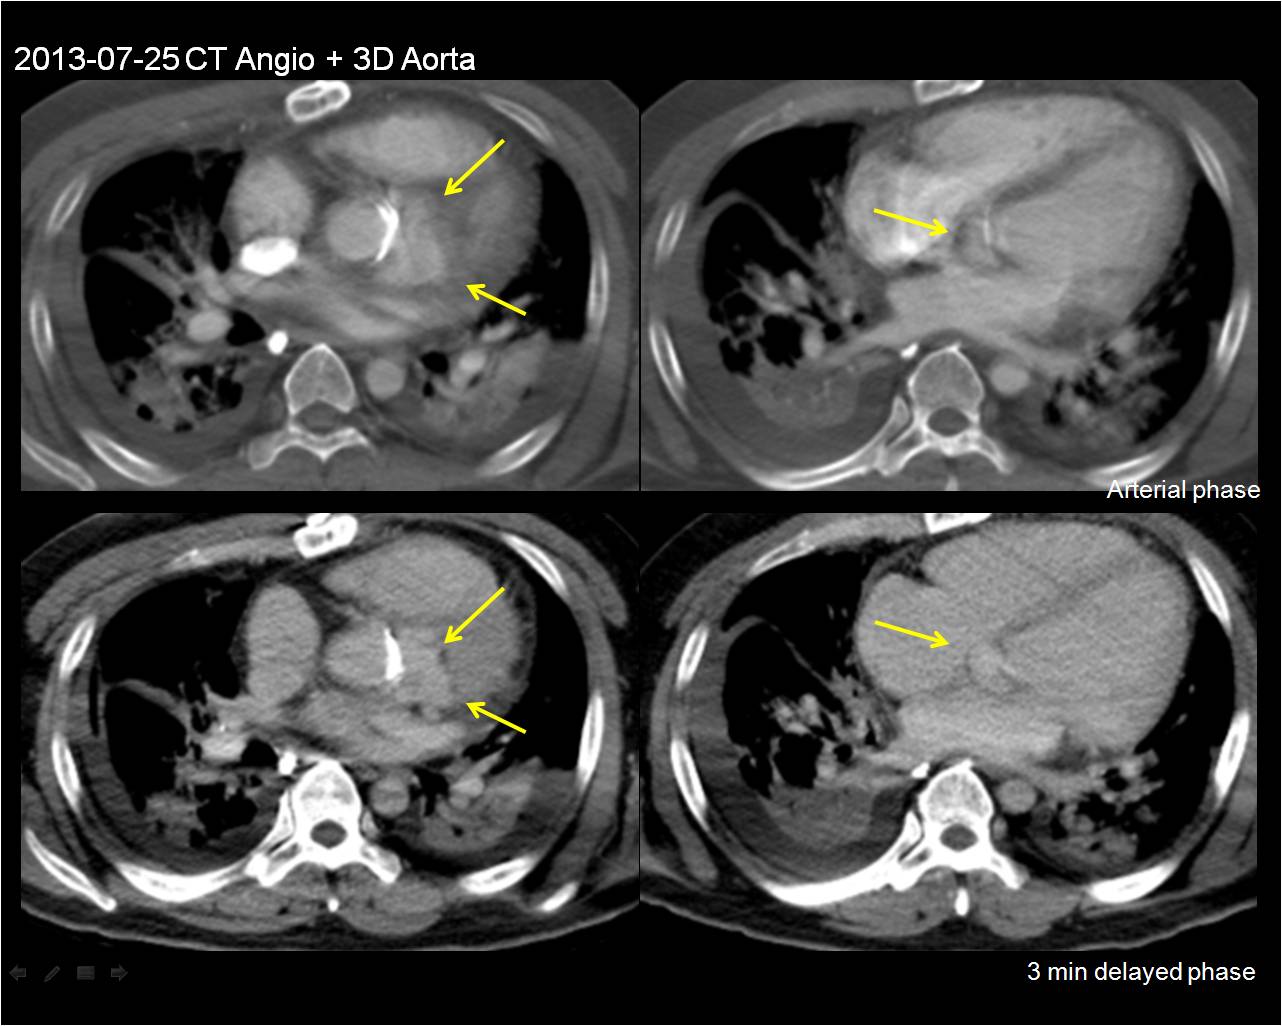

July

F/50 Dizziness

Sung Ho Hwang, Department of Radiology, Korea University Anam Hospital

HIT : 27